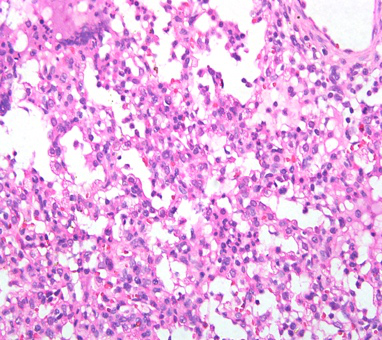

猪场免疫抑制疾病问答